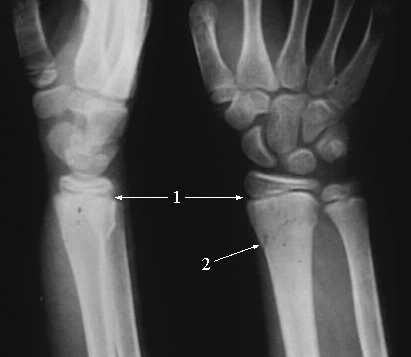

Upper Limbs:Wrist Colles Fracture:

1. Radial Growth Plate

2. Fracture Site at the Lower end of the Radius.